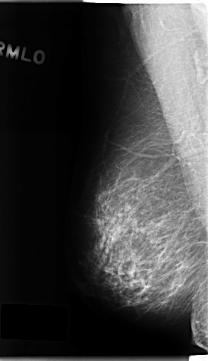

C_0215_1.RIGHT_MLO

RIGHT_MLO LINES 4688 PIXELS_PER_LINE 2704 BITS_PER_PIXEL 12 RESOLUTION 50 NON_OVERLAY